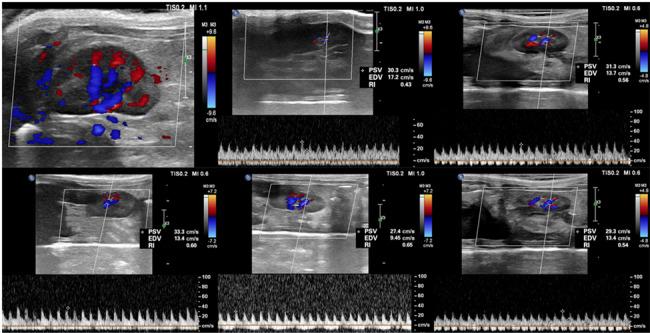

METHODS

In this study, forty-two male Sprague-Dawley (SD) rats were equally divided into two groups: a contrast media (CM) group and a control group, each containing 21 animals. The CM group was administered a tail vein injection of ioversol (370 mg I/ml, 1.5 ml/kg), while the control group received a saline solution in a similar volume. Assessments using IVIM-MRI and Doppler ultrasound were performed 24 h before and at 1, 24, 48, and 72 h post-injection. These assessments aimed to evaluate the true diffusion coefficient (D), pseudo-diffusion coefficient (D), perfusion fraction (f), apparent diffusion coefficient (ADC), and RRI. Concurrently, three rats from each group were sacrificed at these time points for renal histopathology, hypoxia-inducible factor-1α (HIF-1α) expression analysis, and the quantification of serum creatinine (SCr) and blood urea nitrogen (BUN) levels. Receiver operating characteristic (ROC) curves were plotted, and the area under the curve (AUC) was analyzed to evaluate the diagnostic performance of IVIM and RRI in predicting CIN.

Post-ioversol administration, significant declines were noted in the D, D, f, ADC across the renal cortex (CO), outer medulla (OM), and inner medulla (IM) from 1 to 48 h (P < 0.05), with the lowest values observed at 48 h. These parameters began to recover after 72 h. Conversely, RRI values escalated from 1 to 48 h, peaking at 48 h (P < 0.05), and then diminished gradually after 72 h. The control group showed no significant changes in these parameters. Furthermore, a negative correlation was observed between RRI, histopathological grades, HIF-1α expression levels, and the levels of SCr and BUN. In contrast, RRI exhibited a positive correlation with these pathological scores and the levels of SCr and BUN. ROC curve analysis revealed that the combined predictive performance of IVIM and RRI was superior to that of individual parameters.